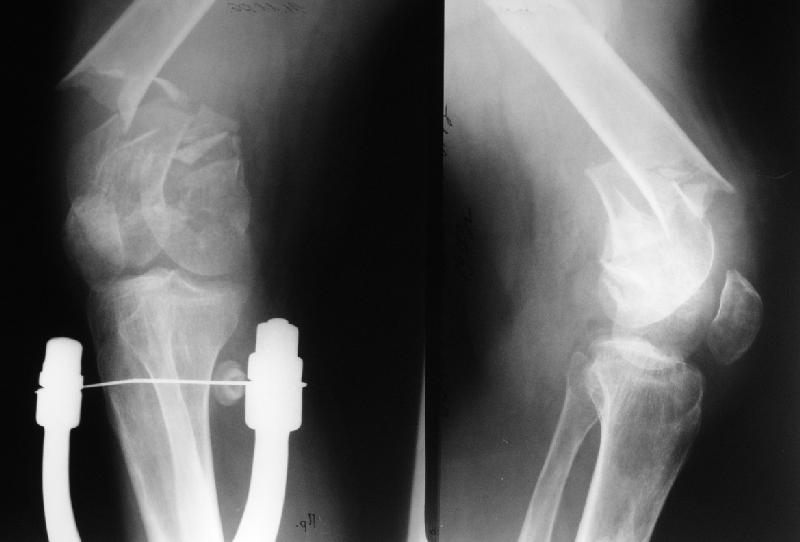

It appears to me that the neck femur and shaft femur are old injuries. I would give preference to the distal femur fracture, but you can only align

the shaft if the malunited midshaft femur fracture is corrected. So my plan:

1. Open reduction and plating of the midshaft femur fracture

2. Distal femur fracture reduction and fixation by indirect reduction if possible, direct reduction if required. I would use locking plate if possible, if not distal femur plate.

Больной поступил в клинику. Дополнительные сведения: диафизарный перелом (открытый)получил 5 лет назад - падение с 5 этажа. Лечился консервативно. Через год стал ходить без трости, хромоты не было, колено гнулось ( со слов больного),В принципе был удовлетворен своим состоянием. 1,5 месяца назад упал в подъезде (в состоянии алкогольного опьянения). Отказался от 2 группы инвалидности - просто не пошел на переосвидетельствование. Живет с мамой (пенсионерка).

Я рекомендую разделить лечение на этапы первым этапом заняться переломом дистального бедра. На мой ввзгляд Дистальныый бедренный гвоздь, введённый через колено - оптимальное решение вопроса. Если нет - плата и шурупы.

после заживления перелома , вторым этапом либо артродез т.б сустава с корригирующей остеотомией, либо протезирование длинным протезом с коррекцией малюниона.